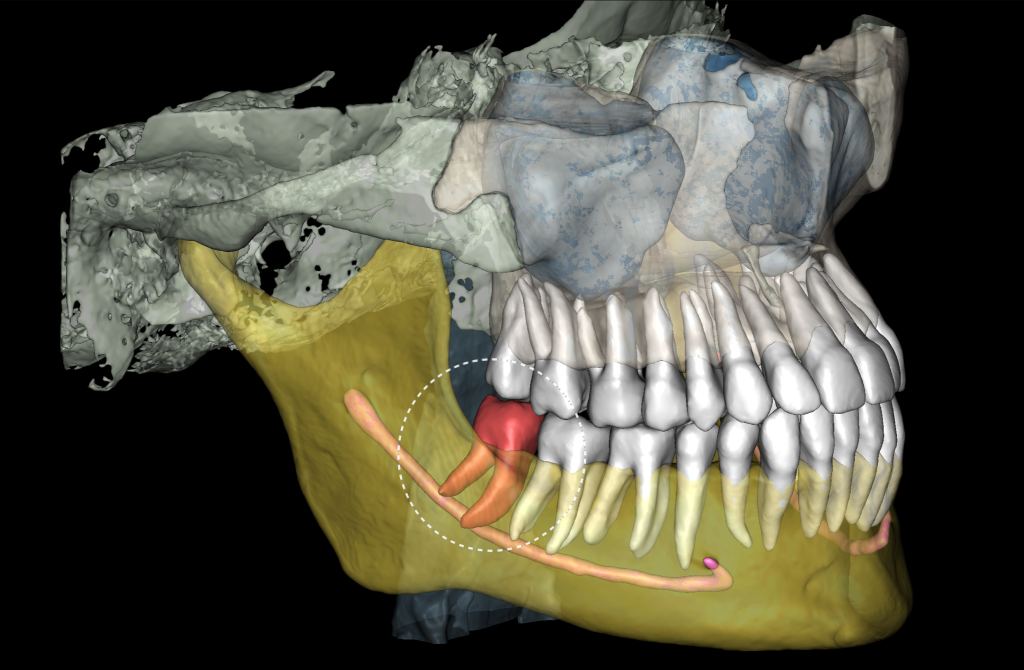

3D реконструкция КЛКЛ является удобным модулем для определения степени сложности предстоящей хирургической манипуляции

А также инструментом визуализации при общении с пациентом

«Отчет по третьим молярам», созданный ИИ Diagnocat — это инструмент, который проводит точный трейсинг нижнечелюстного канала

И выстраивает оптимальную визуализацию в трех плоскостях и помогает врачу оценить расстояние до нижнечелюстного канала